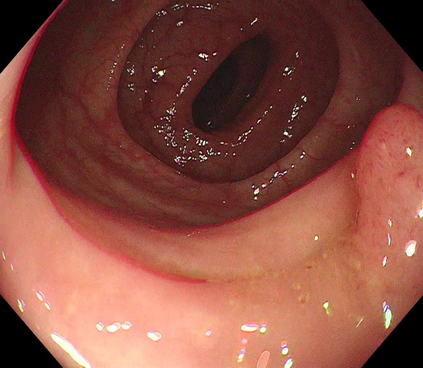

Polyps are early cancer indicators, so assessing occurrences of polyps and their removal is critical. They are observed through a colonoscopy screening procedure that generates a stream of video frames. Segmenting polyps in their natural video screening procedure has several challenges, such as the co-existence of imaging artefacts, motion blur, and floating debris. Most existing polyp segmentation algorithms are developed on curated still image datasets that do not represent real-world colonoscopy. Their performance often degrades on video data. We propose a video polyp segmentation method that performs self-supervised learning as an auxiliary task and a spatial-temporal self-attention mechanism for improved representation learning. Our end-to-end configuration and joint optimisation of losses enable the network to learn more discriminative contextual features in videos. Our experimental results demonstrate an improvement with respect to several state-of-the-art (SOTA) methods. Our ablation study also confirms that the choice of the proposed joint end-to-end training improves network accuracy by over 3% and nearly 10% on both the Dice similarity coefficient and intersection-over-union compared to the recently proposed method PNS+ and Polyp-PVT, respectively. Results on previously unseen video data indicate that the proposed method generalises.